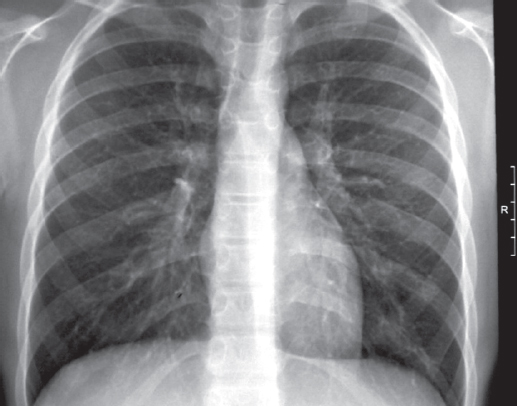

Анамнез заболевания. В процессе диспансерного наблюдения по туберкулезному контакту, в связи с положительной пробой с аллергеном туберкулезным рекомбинантным, проведена впервые мультиспиральная компьютерная томография (МСКТ) органов грудной полости 22.08.2011 (рис. 1) с внутривенным контрастированием. Заключение: «В легких без очаговых и инфильтративных изменений. Выявляются лимфоузлы трахеобронхиальной группы справа (до 8 мм), трахеобронхиальной группы слева (до 7 мм), лимфатические узлы корней легких с двух сторон (до 6 мм), бифуркационной группы (до 7 мм). В структуре лимфатических узлов корней легких и вдоль промежуточного бронха множественные кальцинаты».

Рис. 1. Пациент, 5 лет. Компьютерная томография грудной клетки (туберкулез внутригрудных лимфоузлов) от 22.08.2011

Fig. 1. Patient, 5 years old. Computed tomography of the chest (tuberculosis of the intrathoracic lymph nodes), 22.08.2011